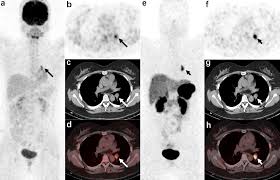

An FDG PET CT scan uses a glucose-based radioactive tracer known as FDG. Since cancer cells and certain infections consume more glucose than normal tissues, the scan highlights abnormal metabolic activity in the body. The Best FDG PET CT Scan in AIIMS can detect disease even at an early stage, when symptoms may not be obvious.

Advanced Imaging Technology for Reliable Results

The Best FDG PET CT Scan in AIIMS is backed by state-of-the-art PET CT scanners that provide high-resolution images and precise metabolic mapping. Modern technology allows doctors to identify even small lesions that might be missed on conventional imaging.